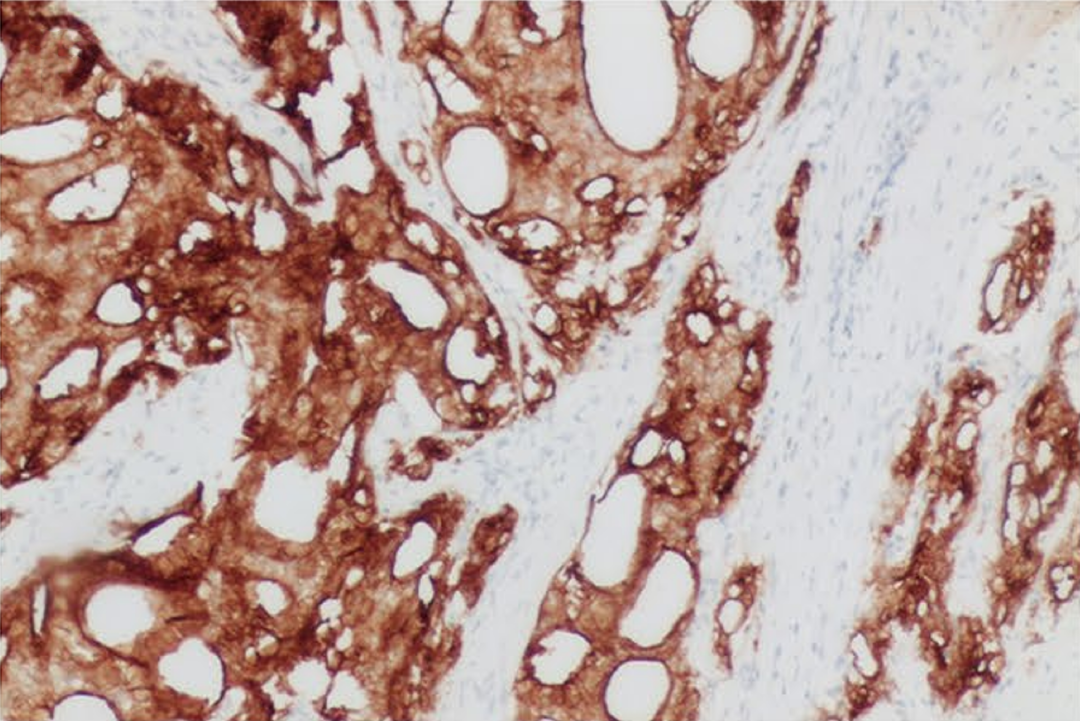

FOLR1

FOLR1 ——叶酸受体 1,属于叶酸受体家族。

定位: 细胞膜。

功能: 在正常组织中主要负责转运叶酸,以维持机体代谢与发育需求。

FOLR1 的过度表达通常与癌症进展加快和患者预后较差有关 [27] 。 在多种实体瘤 (尤其是高级别浆液性卵巢癌、肺腺癌) 中异常高表达,而在正常组织表达受限,因此是备受关注的肿瘤靶向治疗和诊断显像的靶点。

图 16. 人卵巢癌组织的 FOLR1 免疫组化分析 (HY-P81354)。